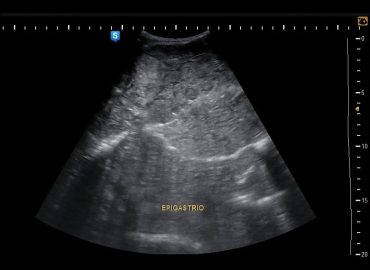

Pte de sexo femenino, 60 años. MC Dolor epigástrico